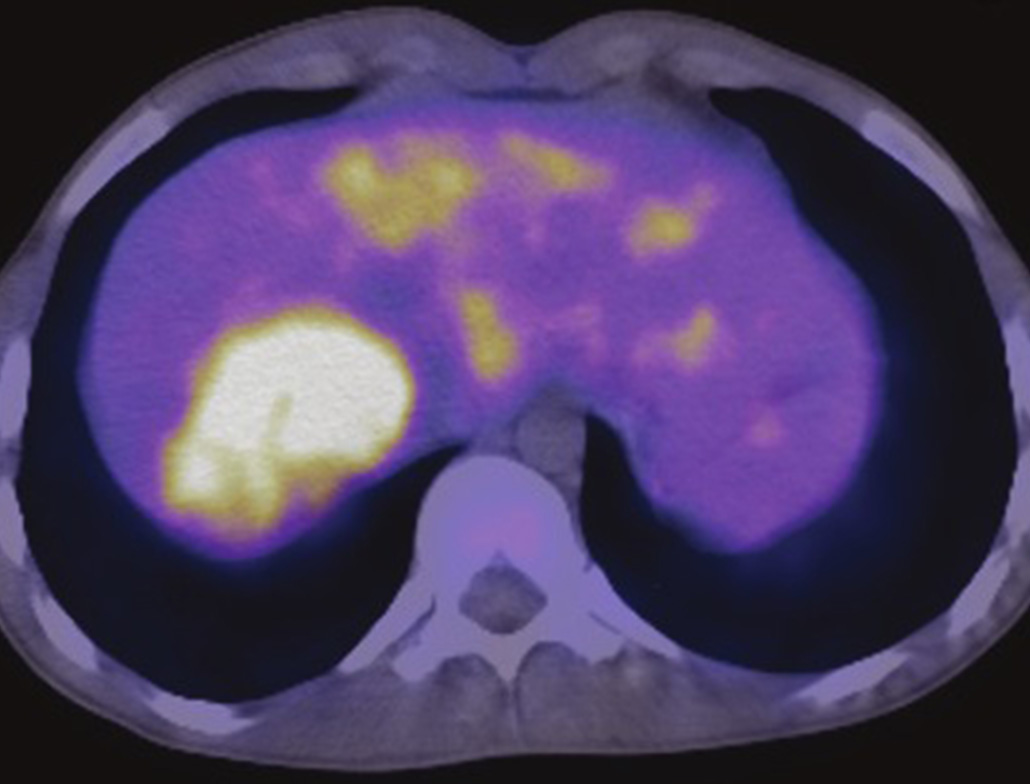

06. 11C-Acetate

Hepatocellular carcinoma (HCC) metabolic imaging and prostate cancer assessment, suitable for PET/CT lipid metabolism pathway detection.